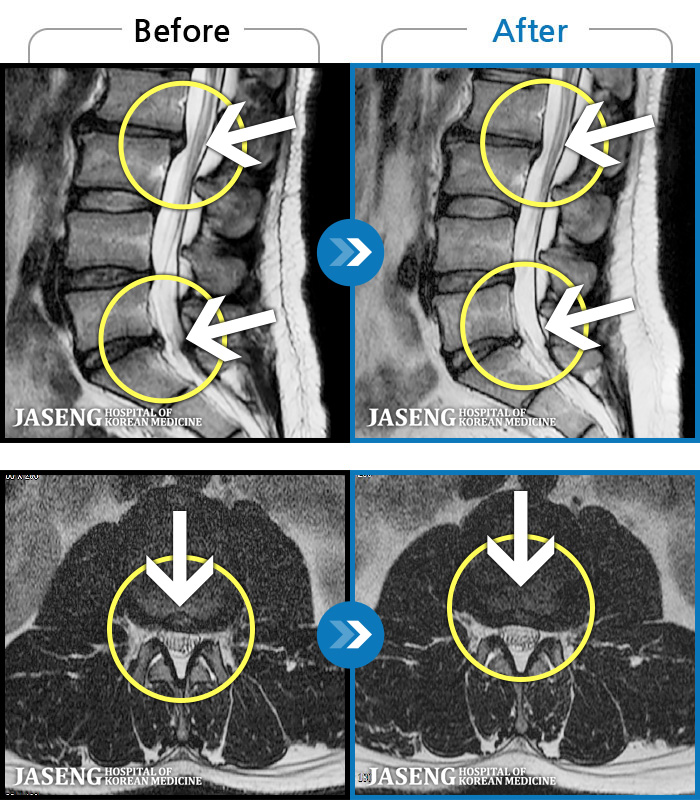

56 MRI ũ ʸ Ȯϼ.

Ƹ ϰ ־.

[õ] 25.03.18~25.07.22

ȯںп Ǹ ǿ ԿǾ, ο ġ ۿ Ƿ ġḦ Ͻñ ٶϴ.

[õ_㸮ũ] Ƹ ϰ ־.